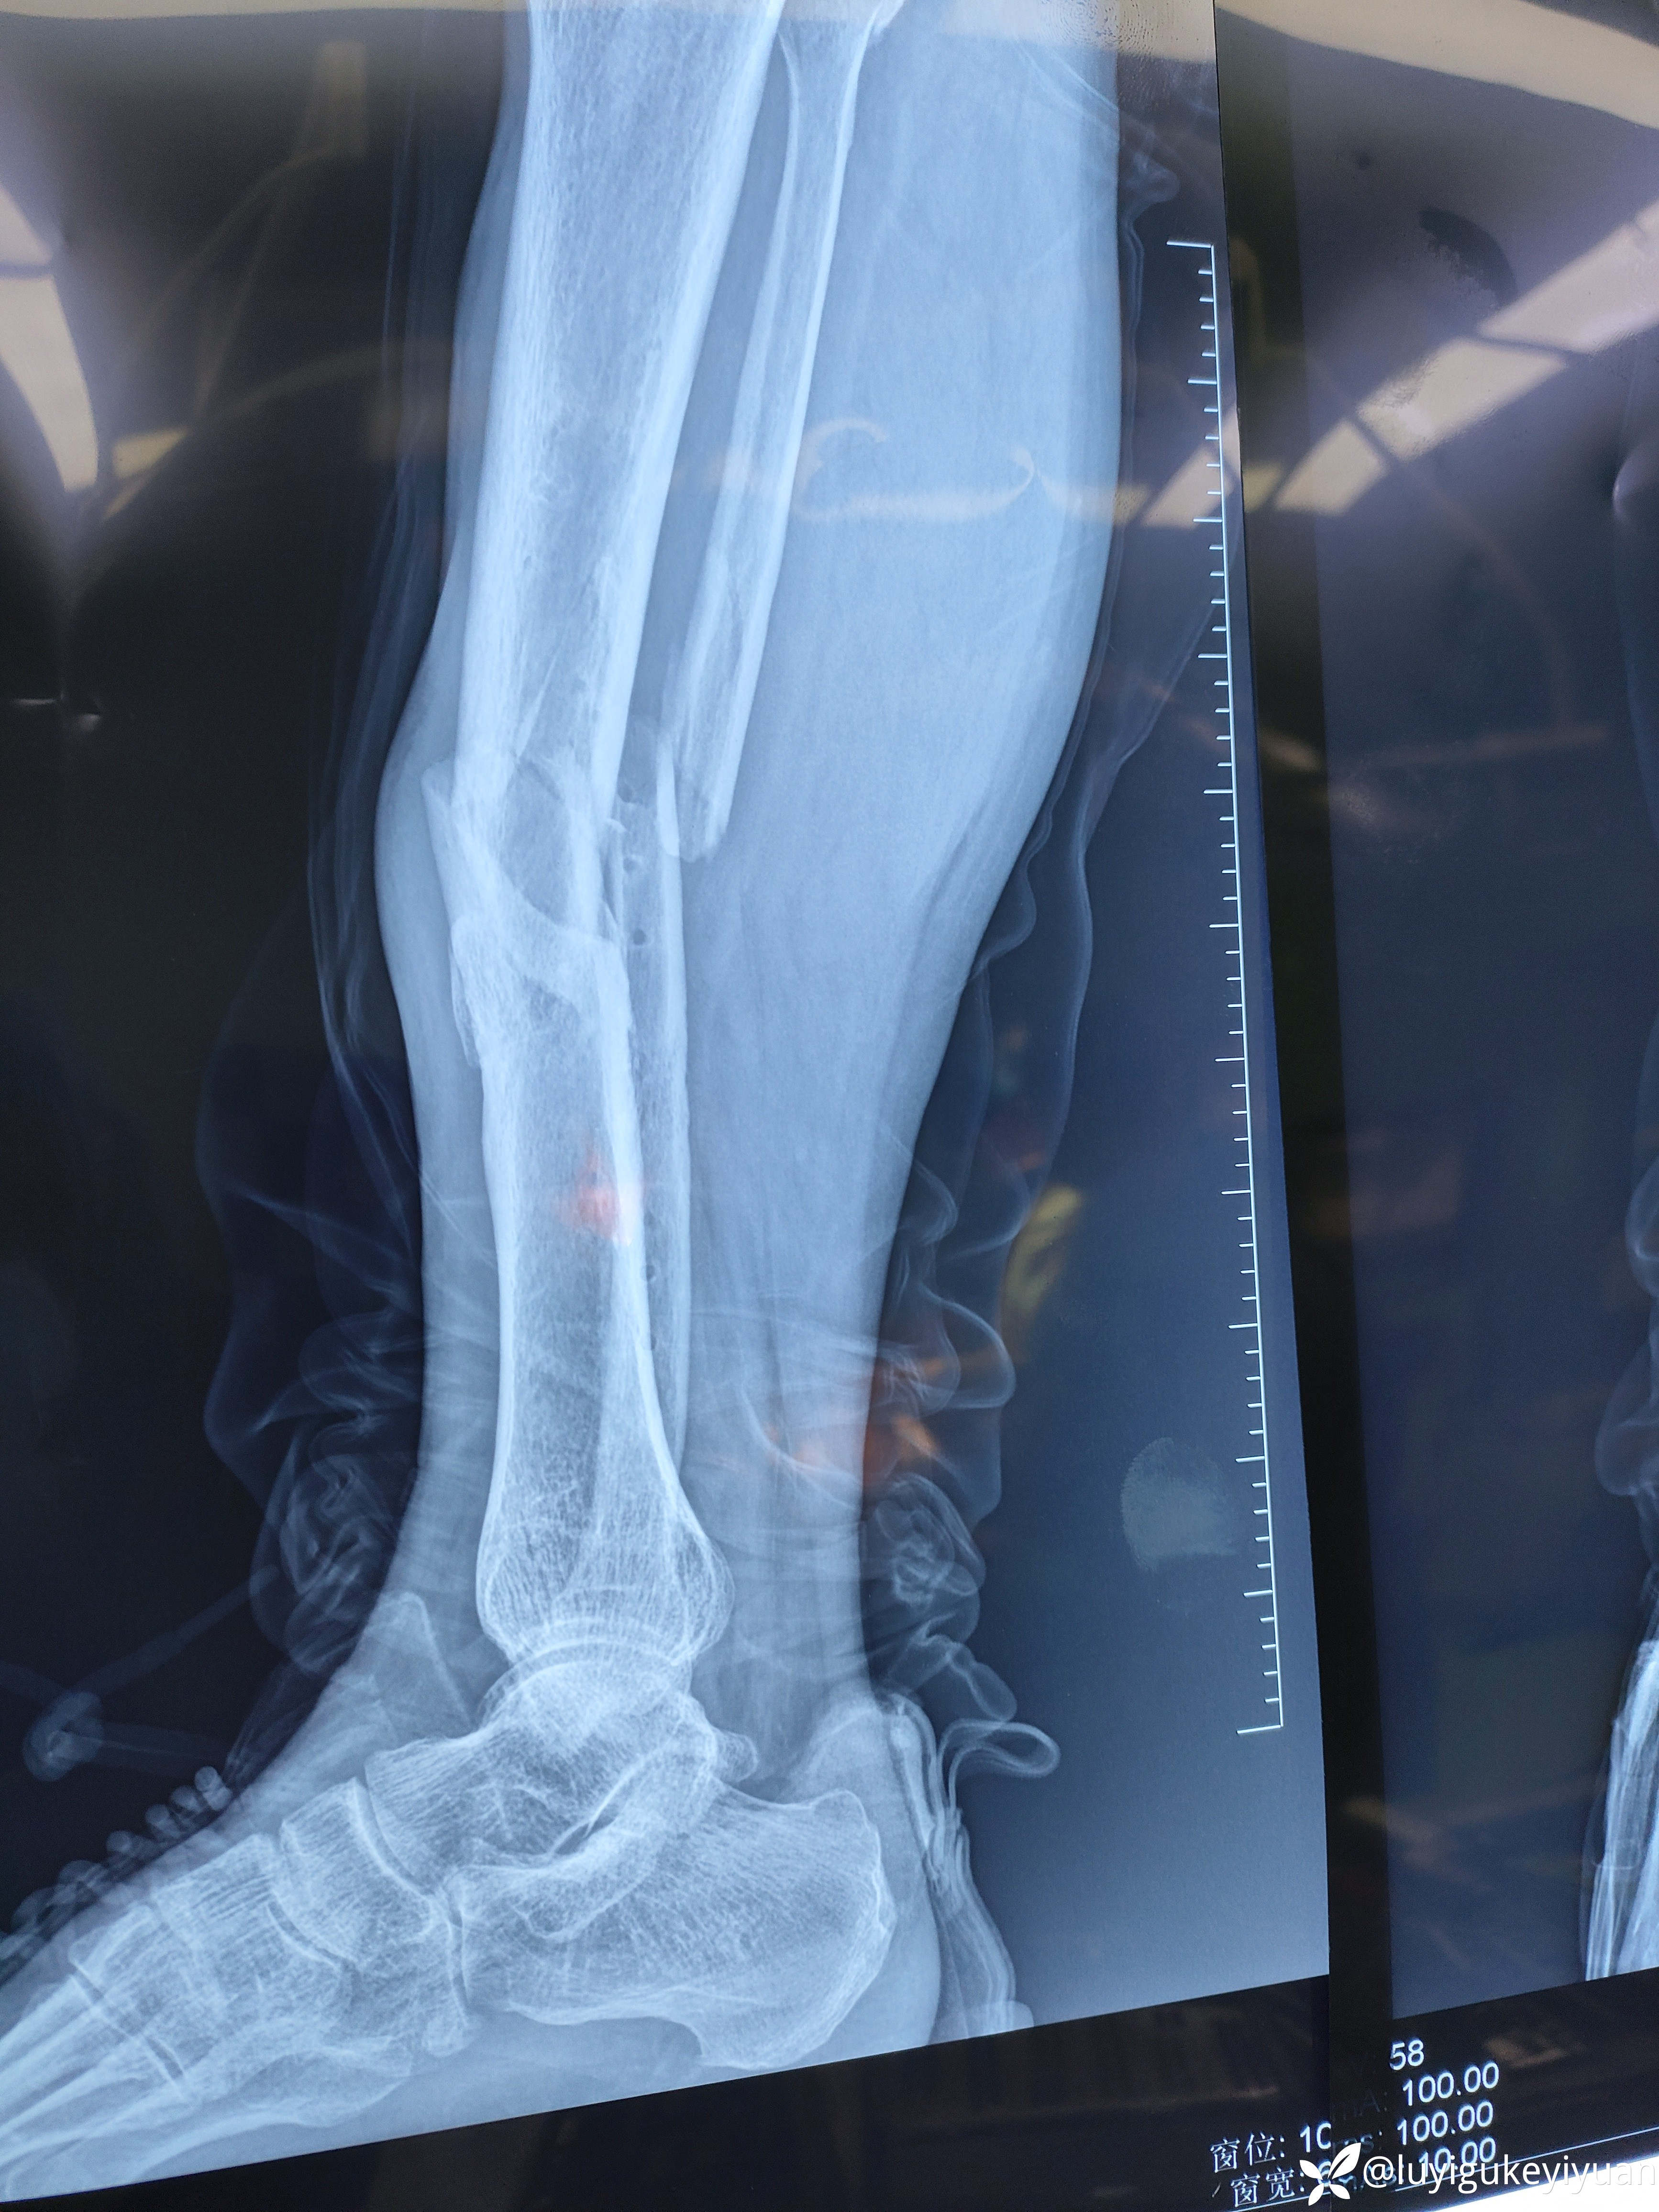

病例胫腓骨二次骨折

医患关系太紧张啊,术前谈话说的好好的,术后骨折部位不一定解剖复位,术后患者家属说手术不成功,真